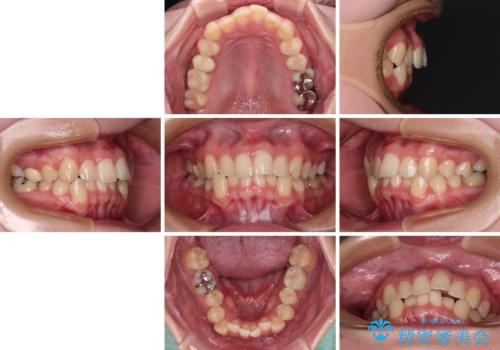

- 30代女性

- 矯正装置

- メタルブラケット

- 治療期間

- 1年3ヶ月

- 前歯のクロスバイトを改善したいとのことで来院された患者様です。

マウスピース矯正では前歯の神経への負担が大きいことを懸念され、ワイヤー装置による矯正治療を行うこととしました。

クロスバイトが改善する際は、前歯しか接触しないため、痛みがあったり食事が取りにくかったりと、不便な時期がありますが、1年強の短期間で無事に治療を終えることができました。